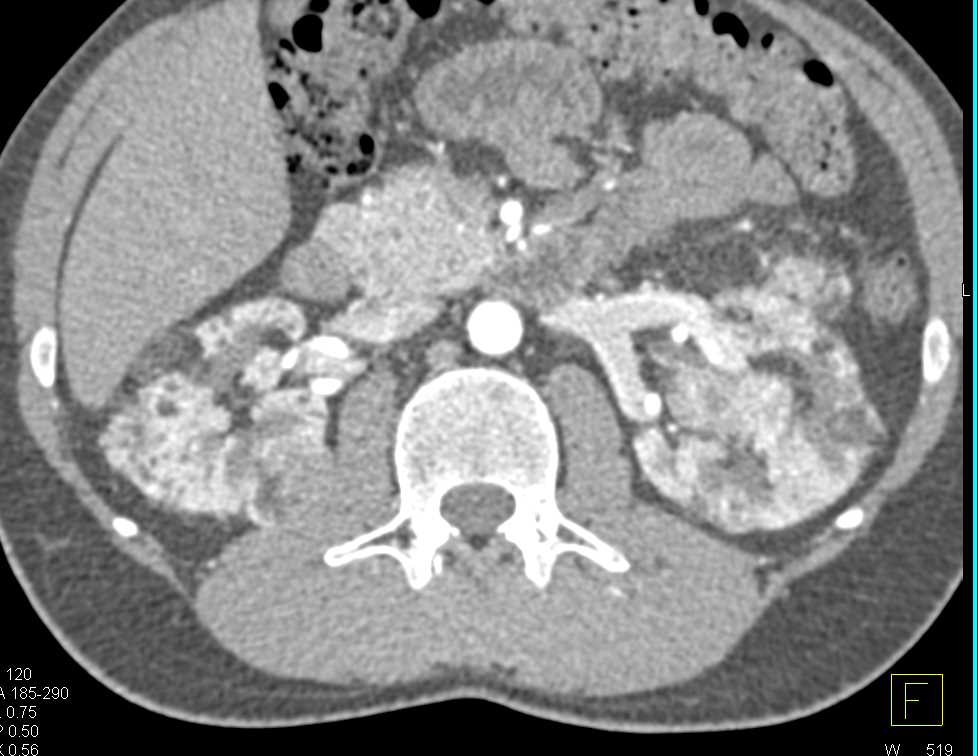

Fat-Fluid Level in the Bladder Following Partial Resection of a Renal Mass